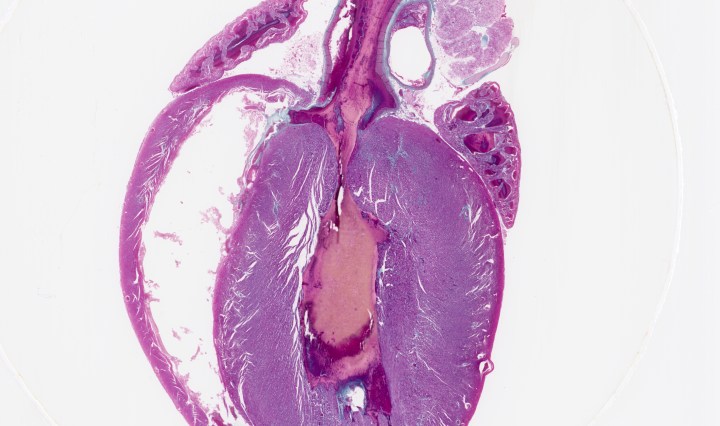

Whole Rat Heart, l.s.

August 12, 2016August 12, 2016 Kit Ng

Continue reading Whole Rat Heart, l.s.